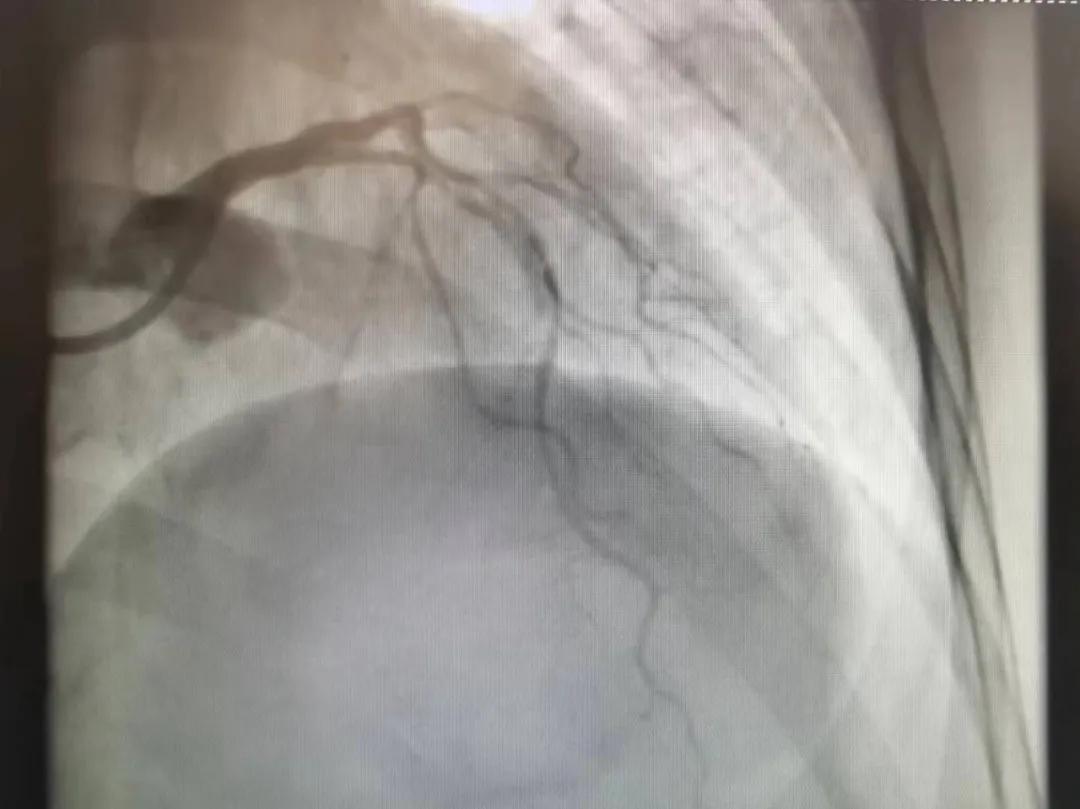

王瑾院長和李慧新主任帶領(lǐng)介入團隊充分評估,決定行前降支冠狀動脈鈣化病變旋磨術(shù),術(shù)中應(yīng)用1.5mm旋磨頭,以15萬-17萬轉(zhuǎn)/分速度共對病變旋磨3次,累計旋磨時間60秒,后復(fù)查造影示鈣化明顯減輕,為后續(xù)操作創(chuàng)造了良好條件,隨后應(yīng)用預(yù)擴張球囊、切割球囊再次處理病變,并順利植入支架1枚,復(fù)查造影顯示支架膨脹及貼壁良好,無夾層、血腫、慢血流等情況,手術(shù)順利完成?;颊咝g(shù)后無不適,胸悶、胸痛癥狀明顯緩解,順利出院。

術(shù)后